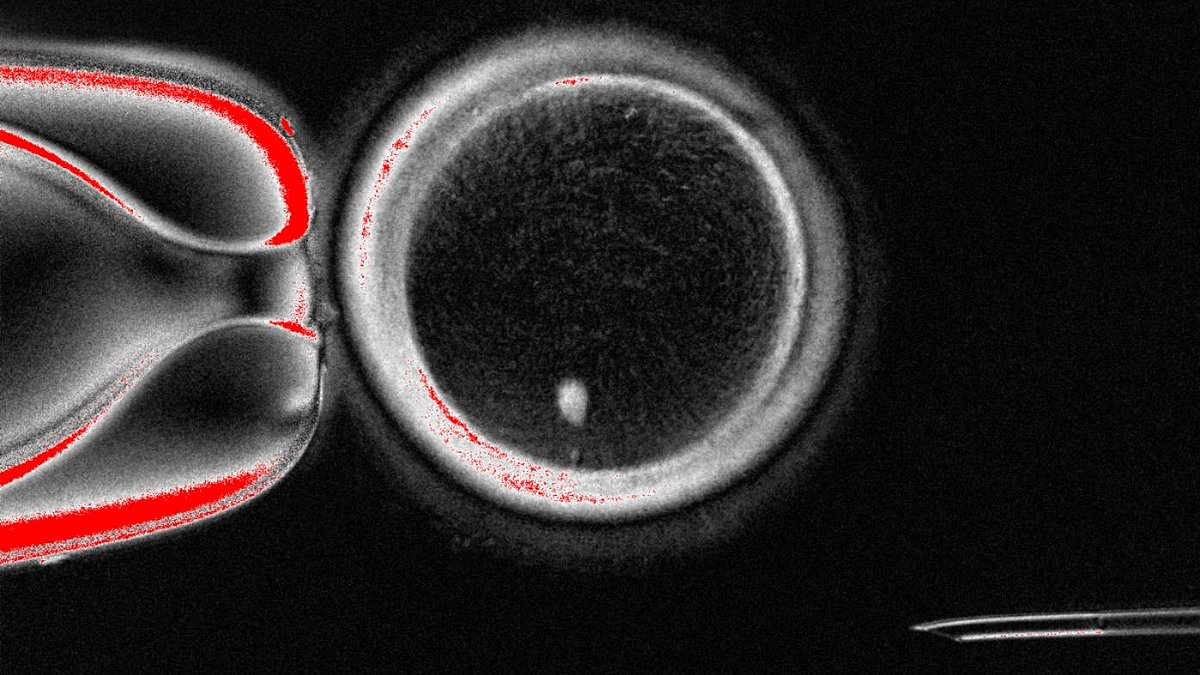

Experts from Oregon Health & Science University have created fertilizable eggs from human skin cells for the very first time

This process involves transferring the nucleus from one of the patient’s own somatic cells, like skin cells, into a donor egg cell that has had its nucleus removed, allowing the cell to transform into a viable egg.

The team resolved this issue by inducing a process they’ve named ‘mitomeiosis’, which mimics natural cell division and causes one set of chromosomes to be discarded.

During tests, the researchers produced 82 functional eggs using this process, which were fertilised in a lab.

In their new study, the team resolved this issue by inducing a process they’ve named ‘mitomeiosis’.

‘[Mitomeiosis] mimics natural cell division and causes one set of chromosomes to be discarded, leaving a functional gamete,’ the researchers explained in a statement.

During tests, the researchers were able to produce 82 functional eggs using this process, which were then fertilised in a lab.

Approximately nine per cent went on to develop the the blastocyst stage of embryo development.